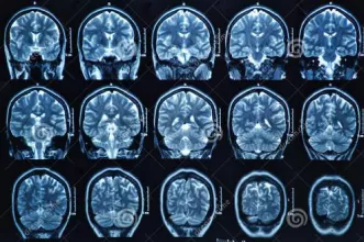

MRI檢查

MRI也就是磁共振成像,屬于斷層成像的一種,它是利用磁共振現象從人體中獲得電磁信號,并重建出人體信息。通過檢查可獲得橫斷面、矢狀面、冠狀面的影像,空間分辨率高,是神經系統、脊柱脊椎部分檢測的第一選擇。

無論是DR還是CT,由于對部分軟組織的分辨率不足,所以軟組織疾病的排查便成了它們的短板,而磁共振的長處恰恰就是清晰顯示軟組織疾病,對于膀胱、直腸、子宮及關節肌肉的檢查優于CT。MRI適用于神經系統病變、心血管系統、胸部病變、全身軟組織病變等。